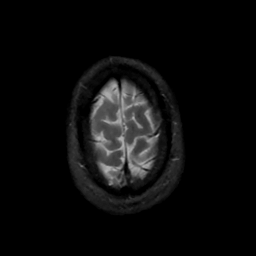

MR Study #15, June 9, 1991 -- Slice #45

[Home][Help][Clinical][Tour 1][Tour 2] Slice 45